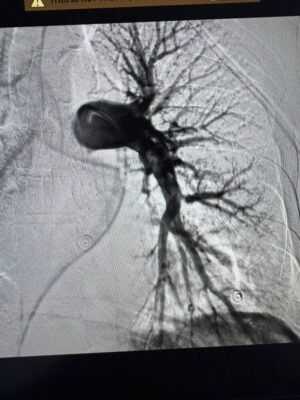

Команда фахівців вирішила провести малоінвазивну ендоваскулярну тромбаспірацію — процедуру, що дозволяє механічно видалити тромб із легеневої артерії без відкритої операції. Методика, яку лікарі нещодавно освоїли на конгресі інтервенційних радіологів у Барселоні, виконувалась під рентгенконтролем за допомогою катетера та спеціальної системи аспірації.

Завдяки швидкому рішенню лікарів та сучасним технологіям, вдалося врятувати життя двом пацієнтам, стан яких був критичним. Уже через кілька годин після втручання обидва пацієнти стабілізувалися та продемонстрували позитивну динаміку.